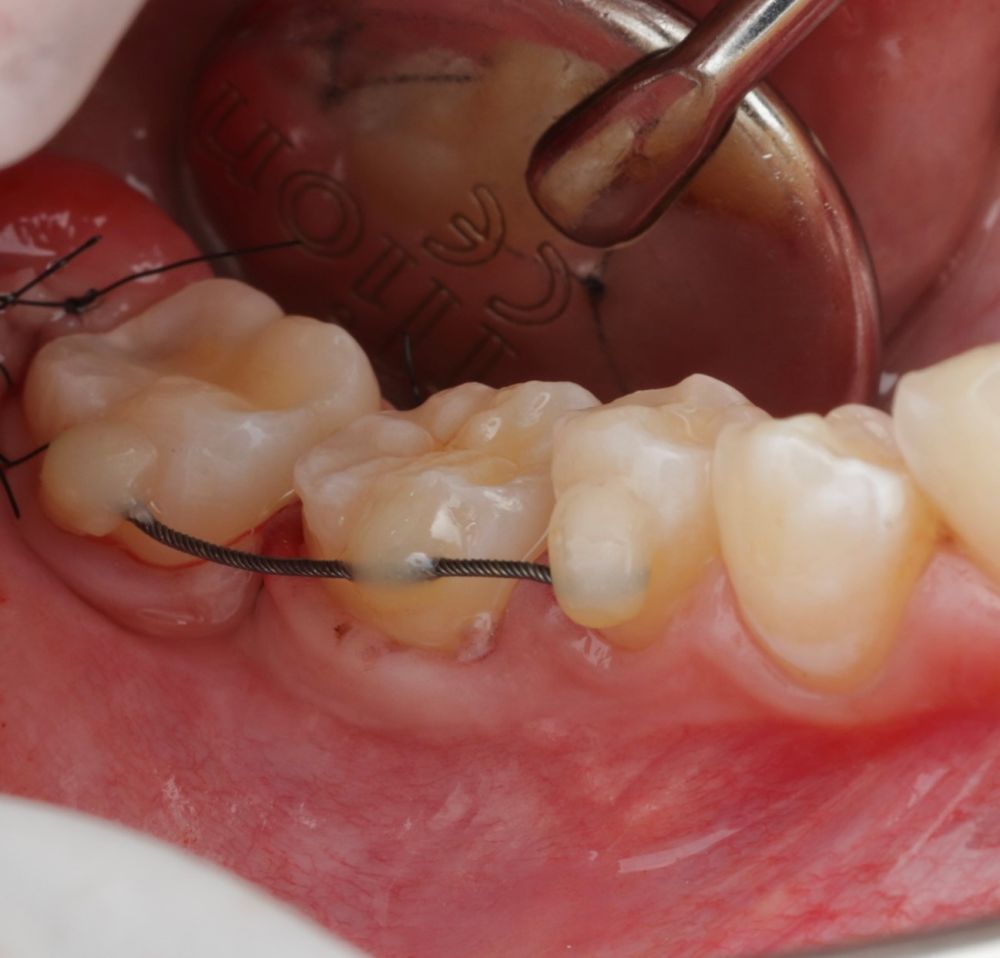

En la revisión sistemática realizada por Barrientos y cols.10, se analizan puntos clave para el protocolo de AD, como los diferentes materiales de fijación del autotrasplante, alambre, resina, sutura, fijación ortodóntica o férulas acrílicas. La tasa de éxito del procedimiento varían entre un 76% y un 95%. La necesidad del tratamiento de conductos, en el 21,1% de dientes no se realizó endodoncia, principalmente en casos con ápice abierto y la tasa de éxito fue más alta cuando la endodoncia se efectuó alrededor del primer mes postoperatorio (en dos semanas: 95,75%; de 7 días a 4 semanas: 90%, y de 6 días a 4 semanas 92,5%. En cuanto a la supervivencia de los dientes trasplantados se apreció que la tasa de éxito disminuye con el paso del tiempo (más de siete años 84%).10.

La confección de la réplica 3D del diente se ha de realizar con material biocompatible y esterilizable mediante radiación gamma y beta. La ventaja del modelo estereolitográfico es minimizar el tiempo extraoral del diente donante, el daño al ligamento periodontal, así como poder remodelar el alveolo receptor sin usar el diente donante5,13,14.